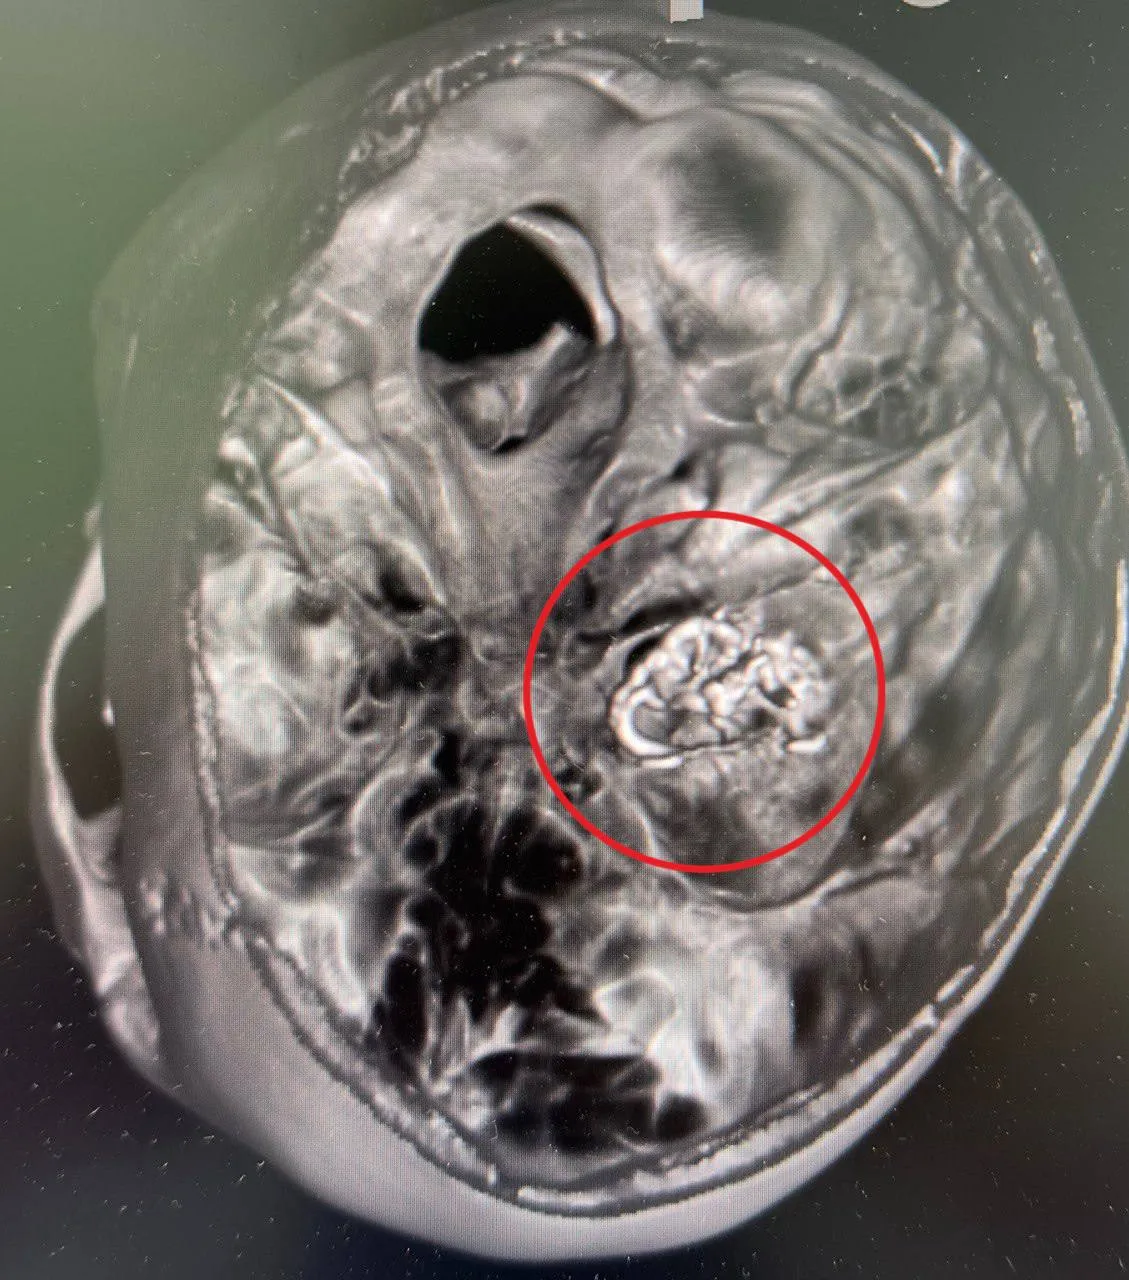

Как уточняется, в клинику с экстренным случаем поступила девочка 16 лет. Она находилась в остром состоянии с кровоизлиянием в мозг. В рамках своей работы медики привели состояние девочки в стабильное, после чего нейрохирурги провели КТ, МРТ и 3D-реконструкцию.

Таким образом они выяснили, откуда идет кровотечение. Патология требовала экстренной операции, поскольку вены и сосуды в переплетении могли образовать «сосудистый клубок».